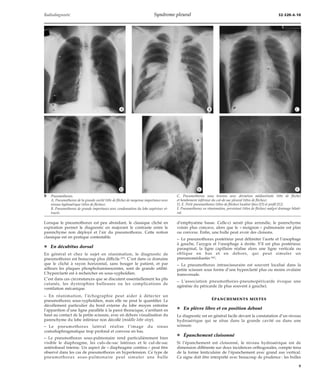

Pneumothorax

La détection d’un pneumothorax de peu d’importance est parfois

difficile, sinon impossible, en radiographie standard et il est

nécessaire d’utiliser des clichés positionnels (rayon horizontal avec

décubitus latéral). La TDM est rarement réalisée dans un but

diagnostique, néanmoins il est certain que sa sensibilité est très

supérieure à la radiographie standard dans les dépistages des petits

pneumothorax. Ainsi est-il possible, en réanimation, de détecter

précocement la survenue d’un pneumothorax sous pressions

expiratoires positives. Après ponction sous TDM, la détection d’un

tout petit pneumothorax est très « sévère » comparée à sa recherche

par radiographie thoracique simple. Le diagnostic de pneumothorax

en TDM est facile, l’air se focalise dans les régions antérieures ou

antérolatérales et décolle le parenchyme pulmonaire de la paroi.

Dans le bilan d’un pneumothorax apparemment « spontané »,

l’emploi de la TDM semble être justifié après une récidive. En effet,

outre l’histiocytose X et la lymphangioléïomyomatose,

pneumopathies infiltratives diffuses, dont la première manifestation

clinique est en général la survenue d’un pneumothorax, la TDM

permet de détecter des affections parenchymateuses pulmonaires,

mal visibles ou invisibles sur la radiographie thoracique standard,

et responsables de pneumothorax. La question de savoir s’il faut

réaliser systématiquement une TDM dans le bilan du pneumothorax

spontané est plus controversée. En effet, faire une relation absolue

entre bulle sous-pleurale et pneumothorax n’est pas tout à fait du

domaine de la réalité, puisque certains malades ayant de

nombreuses bulles paraseptales ne font pas de pneumothorax alors

que d’autres, avec une exploration TDM tout à fait normale en haute

résolution, présentent des récidives de pneumothorax. En fait, la

TDM n’a pas de valeur prédictive en ce qui concerne la récidive du

pneumothorax. Les bulles intrapleurales (blebs) sont en général

invisibles en TDM. Dans ces conditions, d’autres critères cliniques

et paracliniques doivent être pris en considération pour réaliser un

talcage ou une symphyse pleurale chirurgicale en vue d’éviter une

récidive ultérieure (fig 17).

17 Pneumothorax discret et récidivant.

Poches de pneumonectomie [4]

A. Radiographie thoracique en inspiration.

B. Radiographique thoracique en expiration, le pneumothorax devient évident (têtes de flèches).

C. Tomodensitométrie : en inspiration, le pneumothorax est visible, discret, il concerne la scissure. Il existe un col-lapsus

parenchymateux segmentaire très médial dans le lobe inférieur droit.